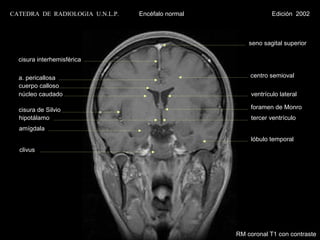

CATEDRA DE RADIOLOGIA U.N.L.P.   Encéfalo normal                Edición 2002

seno sagital superior

cisura interhemisférica

a. pericallosa                                       centro semioval

cuerpo calloso

núcleo caudado                                        ventrículo lateral

cisura de Silvio                                     foramen de Monro

hipotálamo                                            tercer ventrículo

amígdala

lóbulo temporal

clivus

RM coronal T1 con contraste